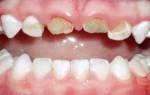

Фото 1. Воспаление десен – причиной может стать распространение бактерий от больных зубов во время операции.

Если причиной зуда и чувствительности стало воспаление слизистой, значит рядом с опустевшей лункой находится зуб, поражённый кариесом. Во время операции по удалению восьмёрки врач обязательно санирует полость рта, но это не даёт гарантии того, что болезнетворные бактерии не попадут в ранку.

Фото 2. Слева – фото до процедуры по удалению зуба, справа видны последствия – изменение прикуса.